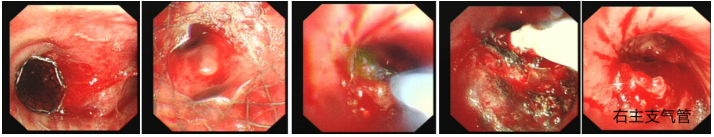

良性中心气道狭窄分为结构性和动力性(6种类型),结构性狭窄包括:管腔内生长(1型),外源性压迫(2型),瘢痕孪缩(3型),扭曲变形(4型);动力性狭窄包括:气道膜部向内膨出(5型),气道软化(6型)。对于动力性狭窄,应考虑用力呼气时的状态,通过操作者的判断,定出最合适、最接近的狭窄程度。治疗方法的制定不仅与气道狭窄程度和长度有关,还与是否存在狭窄过渡段有关。狭窄长度的计算应包括过渡区域。良性气道狭窄形态学分类的诊断方法应通过支气管镜所见及放射学检查来确定。每一个狭窄都可以用4个数字来表示,分别代表部位、类型、狭窄程度、狭窄长度。如:1344代表声门下瘢痕性挛缩性狭窄、狭窄程度>75%、狭窄长度>5 cm,这是一种非常难以处理的良性气道狭窄;2311代表气管瘢痕性蹼状网眼狭窄、狭窄程度<25%、狭窄长度<1 cm,这是一种比较容易处理的良性气道狭窄。热消融技术(APC、电凝、激光)是治疗增生性气道腔内病变(如良性肿瘤和单纯肉芽)的简单、快速的方法。但在治疗瘢痕狭窄病变时,其本身可对气道造成更重、更大范围的损伤,引起更为严重的肉芽组织增生和瘢痕形成,从而导致复发率高,且治疗次数的增加可导致狭窄病变范围增大并最终破坏软骨,导致气道塌陷,使患者彻底失去治愈的机会。电凝和APC仅适合管腔内生长的1型良性中心气道狭窄,并不适合其他类型良性中心气道狭窄的治疗。即便如此,基底部的处理也应避免使用此类治疗方法。针形电刀与气道黏膜接触面极小,不会造成损伤面扩大,瘢痕性气道狭窄的治疗宜选用针形电刀进行切割、松解。因激光也有切割的作用,因此也可选用激光治疗,钬激光、铥激光控制烧灼深度最浅可达0.4 mm,因此更适合良性瘢痕增生性气道狭窄的治疗。冷冻治疗分为冷冻切除(简称冻切,cryoextraction)及冷冻消融(简称冻融,cryoablation)。对于腔内生长的病变可采用冻切治疗,由于容易出血,其安全性不如热消融技术。对于瘢痕病变,冻切技术无法实施,则采用冻融治疗,冻融治疗不促进肉芽组织增生。与热消融相比,冷冻不易导致软骨损伤。通常在热消融治疗接近气道壁时或球囊扩张后采用冻融治疗处理剩余病变,有利于减轻瘢痕再狭窄发生的速度与程度。严重气道狭窄在开通气道前不要使用冻融,因其可引起气道水肿,加重气道狭窄,从而导致窒息。因此,冻融治疗后肺部体征监测及气管镜复查十分重要。机械扩张技术包括球囊扩张和硬质支气管镜扩张,并发症有气道撕裂、再狭窄、出血。(1)球囊扩张:是治疗瘢痕性气道狭窄最主要的技术,其优势是患者治疗后无明显的狭窄段延长,狭窄复发时再狭窄的程度比热消融治疗后轻得多,有利于维持气道复张的疗效。对气管黏膜损伤小,可以在软镜下应用,但需要中断通气。对于挛缩、韧性较强的瘢痕,可先用针形电刀进行切割以松解瘢痕;避免直接暴力球囊扩张,导致气道膜部的撕裂伤。(2)硬质支气管镜扩张:其优势是扩张时不需要中断通气,安全性更好。针对瘢痕肉芽组织增生导致介入治疗后的气道再狭窄,可采用气道狭窄部位局部应用药物的方法抑制瘢痕肉芽组织增生。介入治疗后气道再狭窄可选择的治疗药物有:糖皮质激素、丝裂霉素C、曲尼斯特、紫杉醇等。通过直接植入放射性物质(最常用铱-192)或经过可弯曲支气管镜近距离照射气道瘢痕肉芽组织,促使成纤维细胞凋亡。气道支架置入首选硅酮支架,禁用金属裸支架。支架治疗应作为良性气道狭窄最后选择的治疗技术,启动气道支架治疗的指征:①应用前述各种治疗方法疗效不佳,不能维持气道通畅;②在确定外科手术前临时放置;③外压性气道狭窄;④气道软化、塌陷且无法或不准备行外科手术治疗。病例1:17岁,女性,骨折术后肺炎插管,拔管后(2月14日)气道明显狭窄(图3)。2月15日评估:HR 113次/min,R 24次/min,静息下SpO2 97%(FiO2 50%),咳嗽及说话后喘鸣,有阵发性血氧下降。会诊后拟行急诊介入治疗。2月15日无痛气管镜示:声门下腔黄色及乳白色膜状坏死物,气管上段大量黄色坏死物并管腔重度阻塞,仅见小孔,以冷冻法清除坏死物后管腔通畅(图4)。术后气促明显改善,无需吸氧。病例2:77岁,女性,呼吸困难2个月,加重3天,于2023年12月2日入院(2023年9月气管插管,插管后20余天后拔管)。入院当天查体:HR 125次/min,R 30次/min,静息下SpO2 96%(高流量FiO2 30%),PaCO2 56 mmHg。患者术前影像如图5所示。12月3日查体:HR 140次/min,R 35次/min,BP 190/90 mmHg,SpO2 68%~75%(FiO2 100%),躁动不安,急查血气分析:PaCO2 89 mmHg。紧急床旁无创通气支持下气管镜:气管上段狭窄80%以上,较多黄白黏稠分泌物在狭窄口随呼吸摆动,予抽吸后SpO2升至98%,见狭窄处直径约3 mm,外径5.2 mm,软镜无法进入,遂置入导丝,10#球囊扩张多次,狭窄部位增宽,外径4 mm气管镜引导6.0号气管导管经口插管成功(图6)。插管后患者HR 98次/min,复查血气分析示PaCO2 41 mmHg,氧合指数300 mmHg以上。12月4日气管镜示:右鼻旁路进镜,缓慢退气管导管至声门,距声门3 cm处狭窄,直径7 mm,予12#球囊扩张1 min,2次,未见出血,扩张后直径约12 mm,地塞米松局部保留,气管导管复位(图7)。12月5日拔除气管导管。12月6日气管镜示:气管上段瘢痕狭窄(管径10~12 mm),少许膜状坏死、未见肉芽,予以清除坏死物,7点、11点冻融,术毕注入地塞米松5 mg(图8)。12月13日气管镜示:气管上段瘢痕狭窄(管径12 mm左右),少许膜状坏死、未见肉芽,予以清除坏死物,7点、11点冻融,术毕注入地塞米松5 mg(图9)。